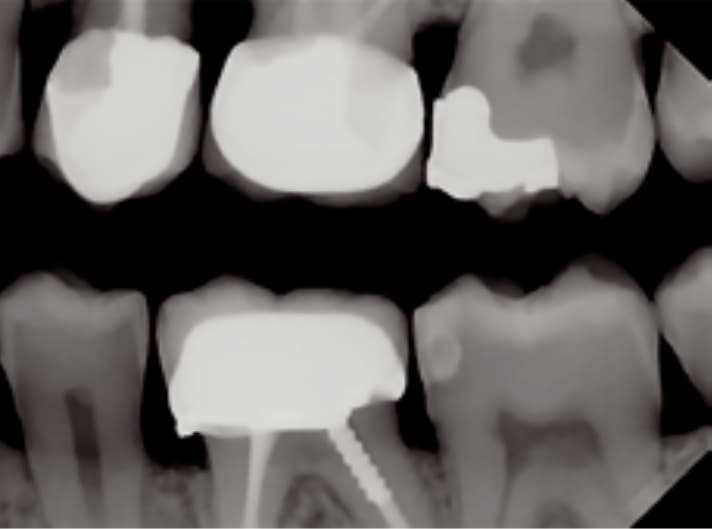

Wysoka rozdzielczość zapewnia dokładną i niezawodną diagnostykę. Technologia wielowarstwowa zapewnia obrazy o niskim poziomie szumów i z wyjątkową ostrością – w zaledwie kilka sekund.